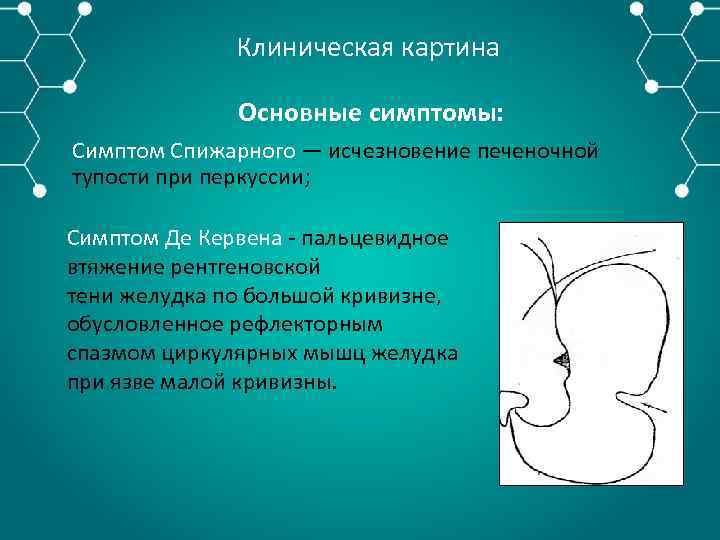

Клиническая картина Основные симптомы: Симптом Спижарного — исчезновение печеночной тупости при перкуссии; Симптом Де Кервена пальцевидное втяжение рентгеновской тени желудка по большой кривизне, обусловленное рефлекторным спазмом циркулярных мышц желудка при язве малой кривизны.